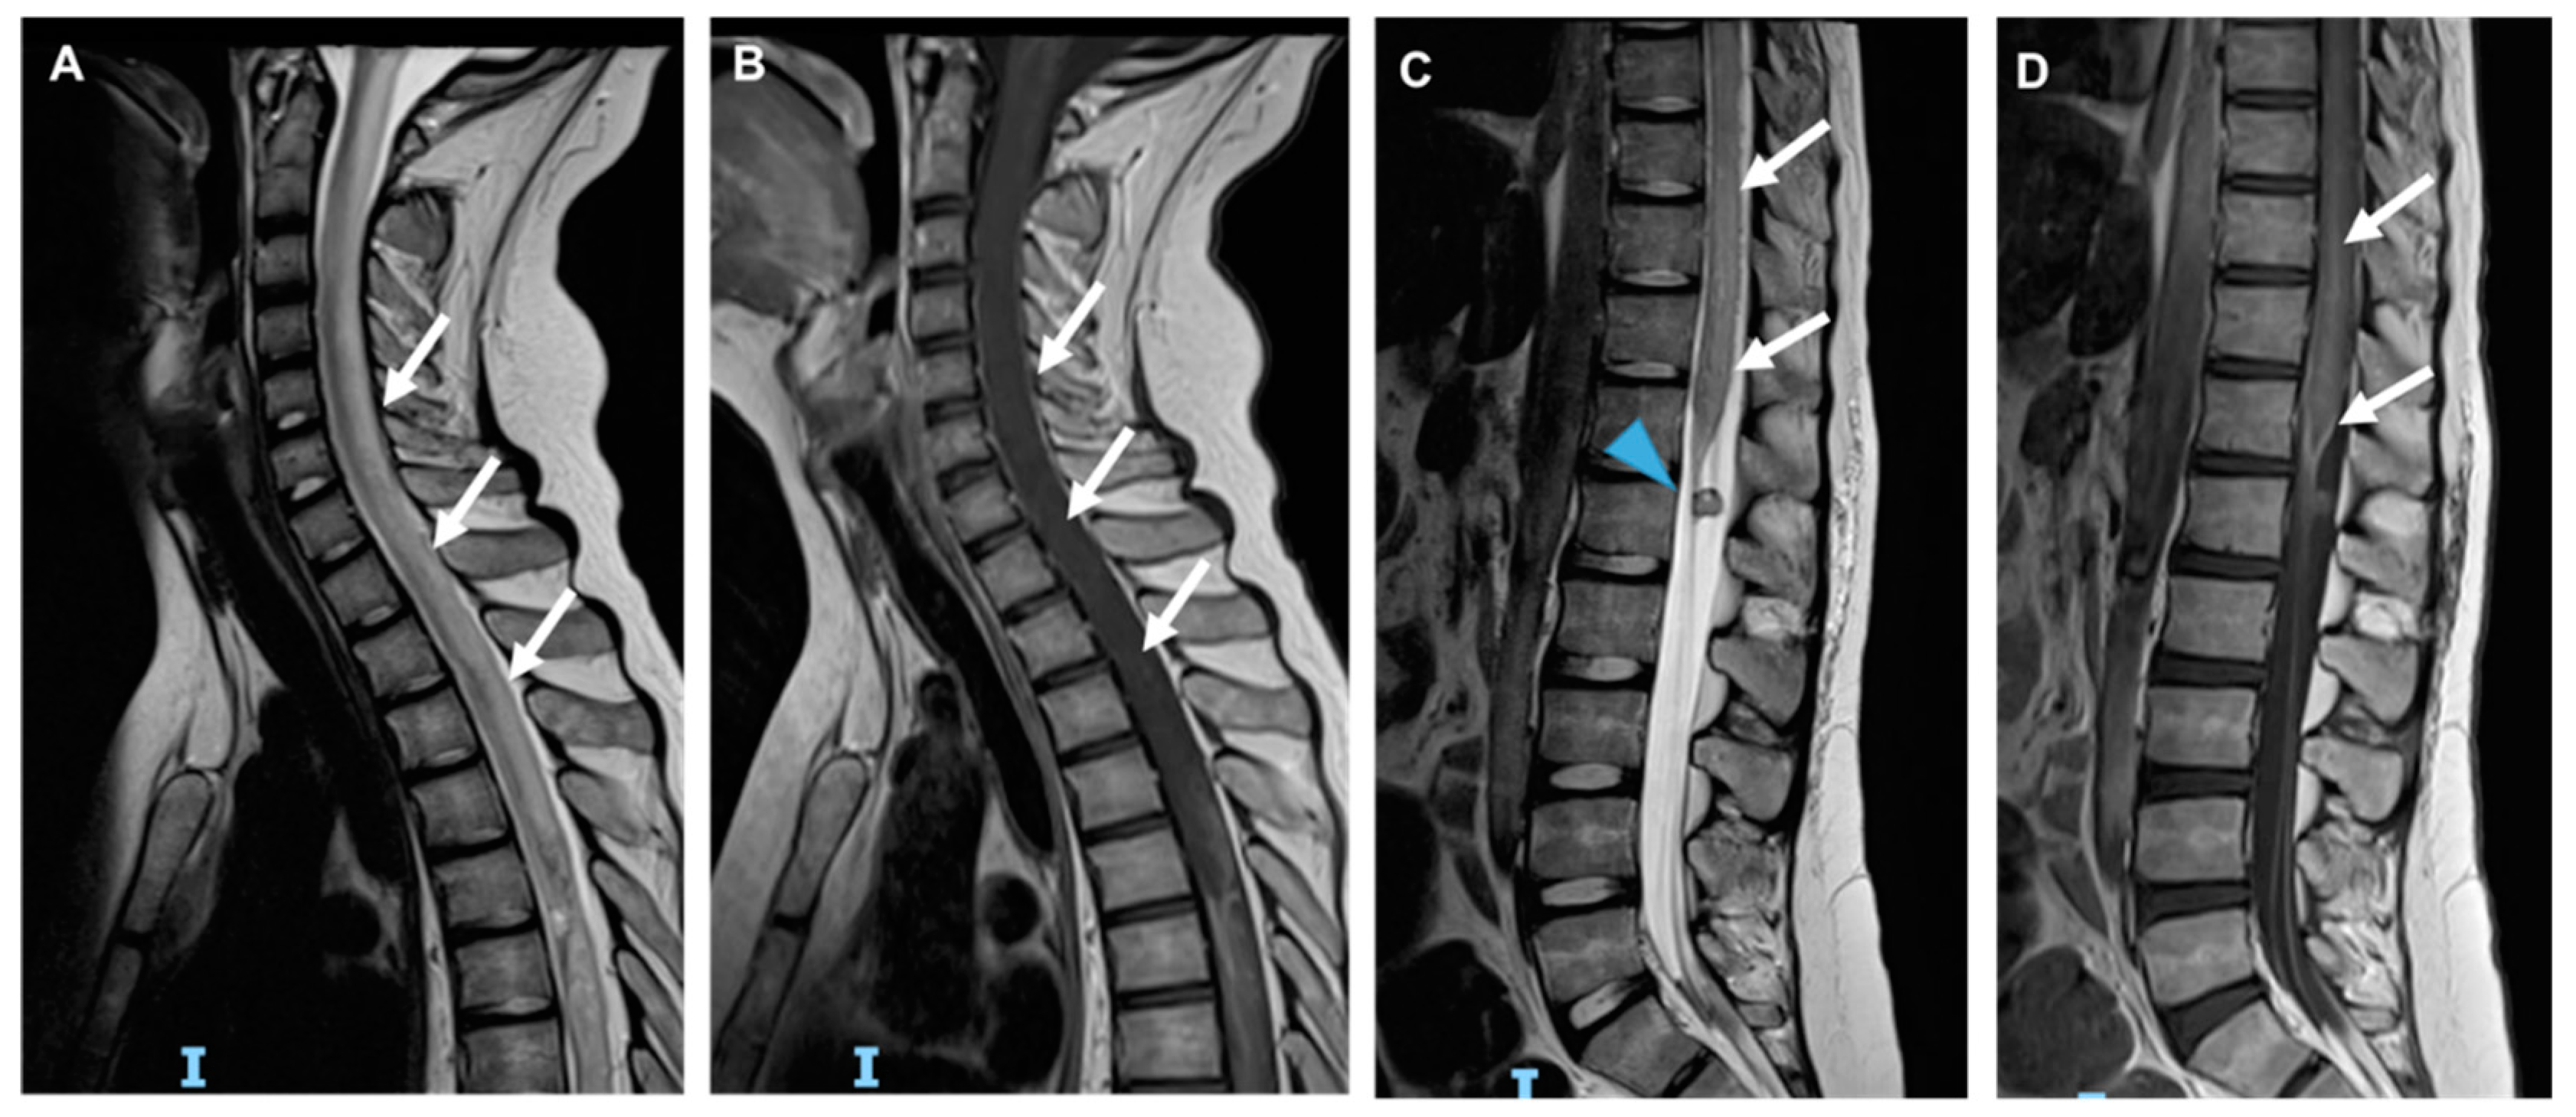

3.3. Stroke-like Migraine Attacks after Radiation Therapy

3.4. Acute Late-Onset Encephalopathy after Radiotherapy (ALERT Syndrome)

3.6. Radiation-Induced Cerebrovascular Disease

- Kerklaan, J.P.; Lycklama á Nijeholt, G.J.; Wiggenraad, R.G.J.; Berghuis, B.; Postma, T.J.; Taphoorn, M.J.B. SMART syndrome: A late reversible complication after radiation therapy for brain tumours. J. Neurol. 2011, 258, 1098–1104. [Google Scholar] [CrossRef] [PubMed] [Green Version]

- Rigamonti, A.; Lauria, G.; Mantero, V.; Filizzolo, M.; Salmaggi, A. SMART (stroke-like migraine attack after radiation therapy) syndrome: A case report with review of the literature. Neurol. Sci. 2016, 37, 157–161. [Google Scholar] [CrossRef]

- Armstrong, A.E.; Gillan, E.; Di Mario, F.J. SMART Syndrome (Stroke-Like Migraine Attacks After Radiation Therapy) in Adult and Pediatric Patients. J. Child Neurol. 2014, 29, 336–341. [Google Scholar] [CrossRef]

- Black, D.F.; Morris, J.M.; Lindell, E.P.; Krecke, K.N.; Worrell, G.A.; Bartleson, J.D.; Lachance, D.H. Stroke-Like Migraine Attacks after Radiation Therapy (SMART) Syndrome Is Not Always Completely Reversible: A Case Series. Am. J. Neuroradiol. 2013, 34, 2298–2303. [Google Scholar] [CrossRef] [Green Version]

- Di Stefano, A.L.; Berzero, G.; Vitali, P.; Galimberti, C.A.; Ducray, F.; Ceroni, M.; Bastianello, S.; Colombo, A.A.; Simoncelli, A.; Brunelli, M.C.; et al. Acute late-onset encephalopathy after radiotherapy: An unusual life-threatening complication. Neurology 2013, 81, 1014–1017. [Google Scholar] [CrossRef] [PubMed]

- Ito, H.; Mori, K.; Kagami, S. Neuroimaging of stroke-like episodes in MELAS. Brain Dev. 2011, 33, 283–288. [Google Scholar] [CrossRef] [PubMed]

- Brada, M.; Ashley, S.; Ford, D.; Traish, D.; Burchell, L.; Rajan, B. Cerebrovascular mortality in patients with pituitary adenoma: Cerebrovascular Mortality in Patients with Pituitary Adenoma. Clin. Endocrinol. 2002, 57, 713–717. [Google Scholar] [CrossRef] [PubMed]

- Roongpiboonsopit, D.; Kuijf, H.J.; Charidimou, A.; Xiong, L.; Vashkevich, A.; Martinez-Ramirez, S.; Shih, H.A.; Gill, C.M.; Viswanathan, A.; Dietrich, J. Evolution of cerebral microbleeds after cranial irradiation in medulloblastoma patients. Neurology 2017, 88, 789–796. [Google Scholar] [CrossRef] [Green Version]

- Murphy, E.S.; Xie, H.; Merchant, T.E.; Yu, J.S.; Chao, S.T.; Suh, J.H. Review of cranial radiotherapy-induced vasculopathy. J. Neuro-Oncol. 2015, 122, 421–429. [Google Scholar] [CrossRef]

- Bavle, A.; Srinivasan, A.; Choudhry, F.; Anderson, M.; Confer, M.; Simpson, H.; Gavula, T.; Thompson, J.S.; Clifton, S.; Gross, N.L.; et al. Systematic review of the incidence and risk factors for cerebral vasculopathy and stroke after cranial proton and photon radiation for childhood brain tumors. Neuro-Oncol. Pract. 2021, 8, 31–39. [Google Scholar] [CrossRef]